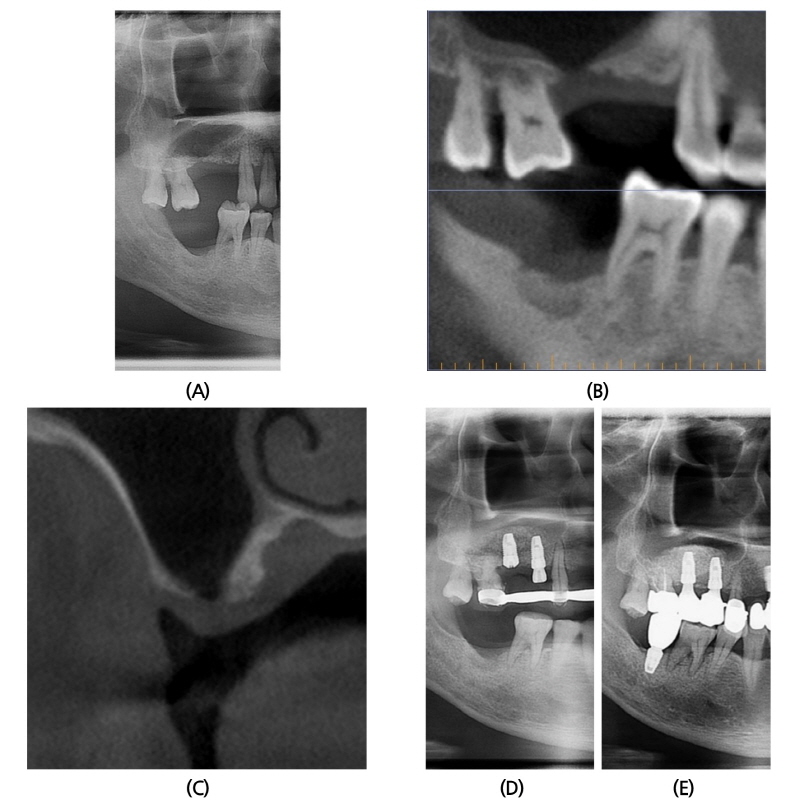

2014년 9월 23일 48세 남성이 전반적인 잇몸 치료 및 임플란트 상담 받고 싶다는 주소로 본과 내원하였다(Fig. 3A). 환자는 특기할 내과적 기왕력 및 수술 병력 없었으며, 내원 당시 #14, 15, 47 missing 상태였다. 수술 전 촬영한 CBCT 소견상, #14 부위는 crestal까지 pneumatization되어 있었고, #15 부위는 잔존 치조골 없이 지름 5 mm 정도 Schneiderian membrane과 gingival periosteum이 유합되어 있었다(Fig. 3B, 3C). 2014년 11월 25일 #14, 15 부위에 상악동 골이식과 임플란트 동시 식립술을 시행하였다(Fig. 3D). CBCT 소견과 동일하게 #15 임플란트 식립 부위에 Schneiderian membrane이 노출되어 있었고, gingival periosteum과 유합되어 있는 것을 조심스럽게 박리, 분리하여 그 사이로 골이식을 시행하였다. 골이식재로 ICB® 1.5 g과 MBCP® 0.75 g을 혼합하여 사용하였으며, Bone window를 opening하면서 채취한 cortical bone을 다시 덮어주었다. #15 식립 후 drilling 시 나온 bone chip으로 soft tissue engage 되지 못하도록 상부에 bone graft를 시행하였다. #14, 15 부위에 임플란트는 Implantium® (Ø4.3 × 10 mm, drilling Ø4.3 mm/ Ø4.8 × 10 mm, drilling Ø4.0 mm) 식립하였다. 수술 후 2년 후에도 임상적, 방사선학적으로 양호한 상태를 보이고 있다(Fig. 3E).